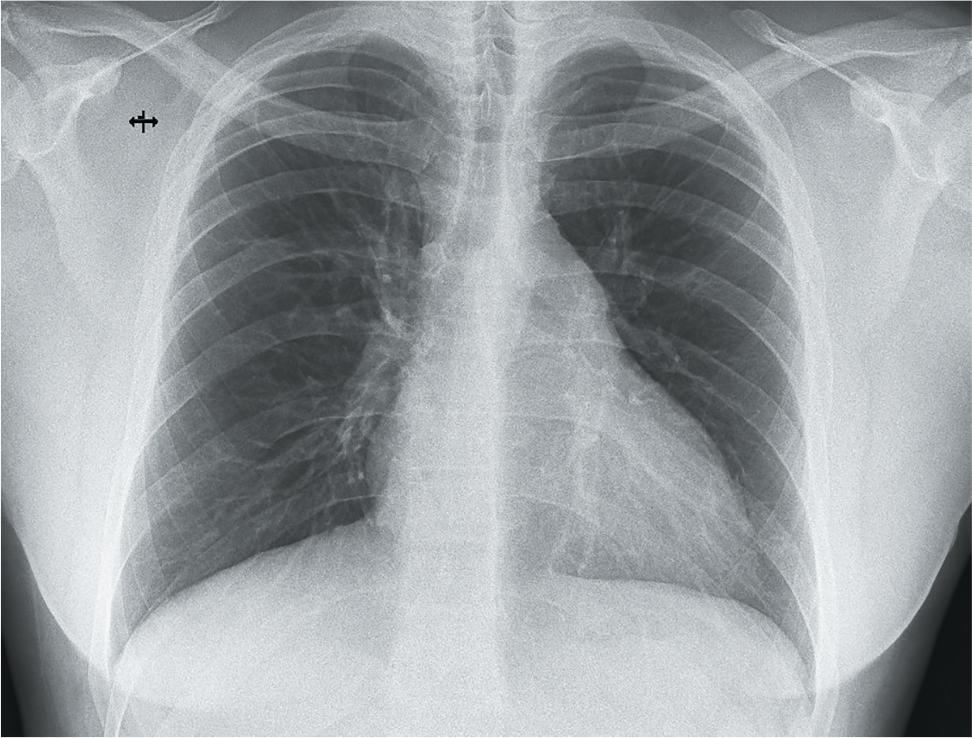

Upon initial evaluation at our clinic, the patient presented with moderate dyspnoea, NYHA II (New York Heart Association Functional Classification), especially with moderate exertion. A 6-min walking test was performed, and the patient managed to walk 450 m, with dyspnoea of 5/10 on the Borg scale, and SpO2 of 98% at the beginning and 93% at the end of the test. The chest X-ray revealed cardiomegaly, with clear lung fields (Figure 1).

Chest X-ray showing cardiomegaly with clear lung fields.